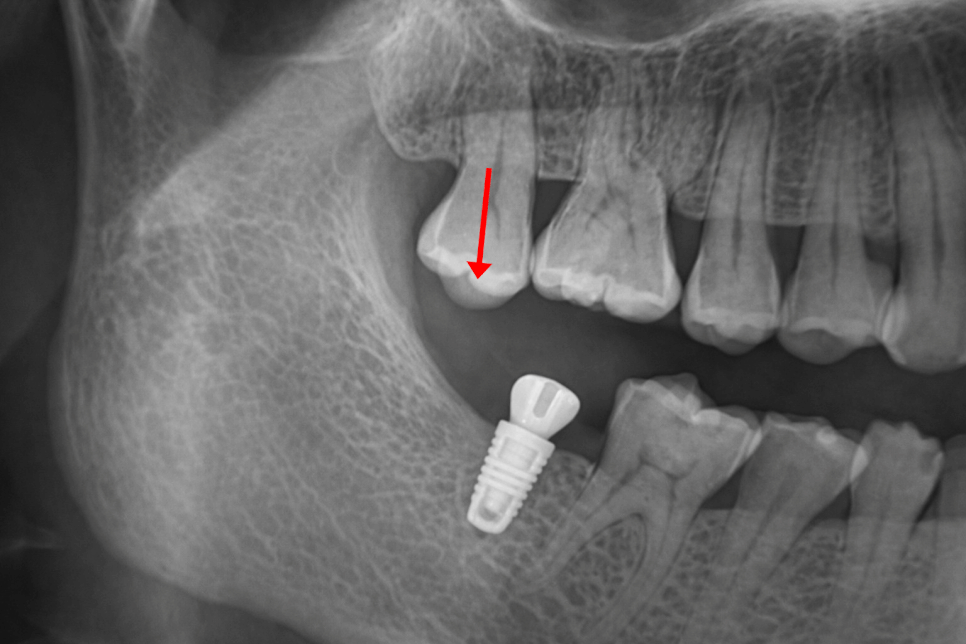

치아가 빠진 자리를 오랜 기간 방치하게 되면

구강 전체의 균형에 영향을 미칠 수 있습니다.

우선 치아가 빠진 부위의

치조골은 점차 흡수되기 시작하며

치아가 존재할 때는 저작압이 전달되면서

뼈가 유지되지만 치아가 사라지면

해당 부위의 자극이 줄어들어

시간이 지날수록 뼈의 양과 높이 감소하게 됩니다.

이러한 변화를 이후 임플란트를 할 때

뼈이식이 필요해지는 원인이 되기도 합니다.

더불어 인접치에도 영향을 줄 수 있으며

비어있는 공간으로 인접치가 기울어지거나

맞물리던 대합치가 위아래로 정출되는

현상이 나타날 수 있으며

이는 교합의 균형을 무너뜨려

저작 기능의 불편함을 일으킬 수 있습니다.

이처럼 구강 구조 전반의 변화를 일으킬 수 있으므로

가능한 한 적절한 시기에

치료 계획을 세우는 것이 중요합니다.